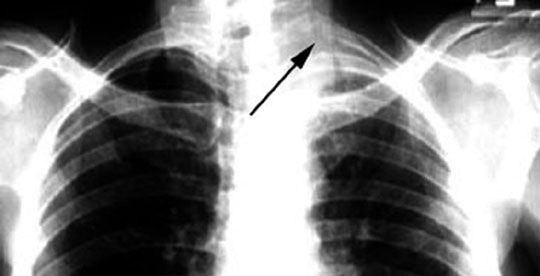

72 year old male presents to Rheumatologist for left shoulder pain.

Findings:

• Apical shadow

• Apical cap

• Destruction of posterior first two ribs

• Shoulder droop: Brachial plexus involvement

Diagnosis

Pancoast Tumor